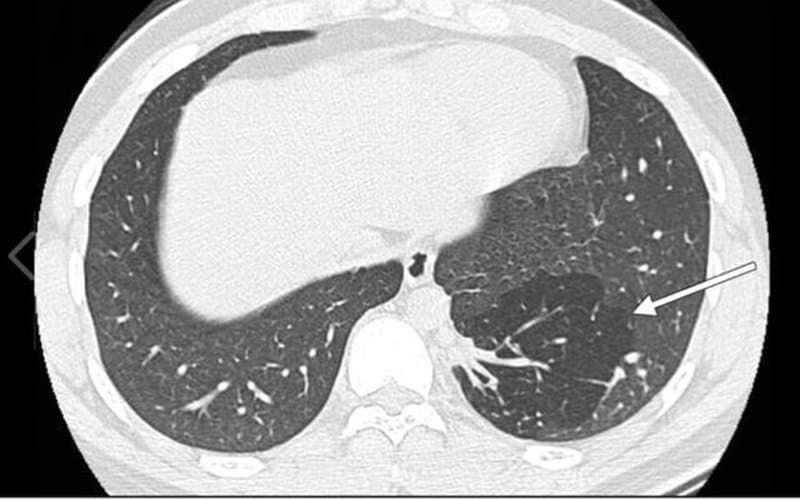

- Khảo sát đặc điểm, vị trí, kích thước, mật độ của các tổn thương bệnh lý ở phổi, trung thất, thành ngực.

- Phát hiện vị trí, kích thước, mật độ của tổn thương;